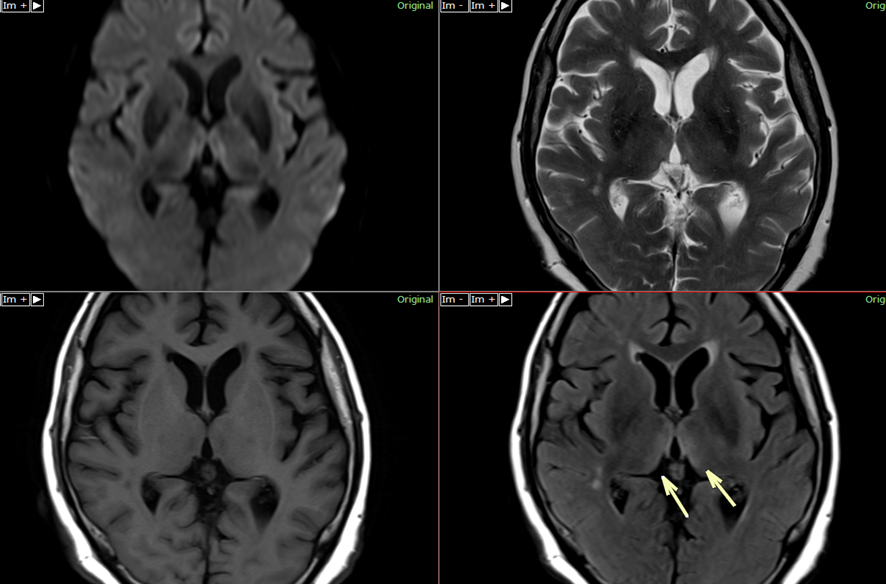

場合によっては、医師が発達検査や神経学的検査を行うこともあります。たとえば、MRI または CT スキャンを注文する場合があります。これは、脳の外観と大きさを検査するのに役立ちます。また、臨床検査を依頼することもあります。これは、遺伝的疾患や染色体疾患をチェックするのに役立ちます。